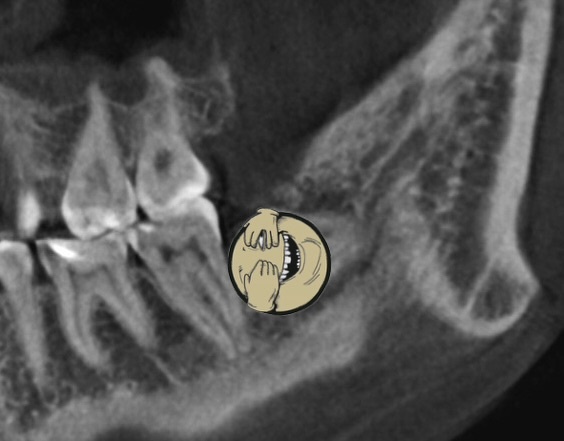

Места нет (скрин - лишь пример, тут 8 зуб вообще разрушен и наклонён в сторону 7)